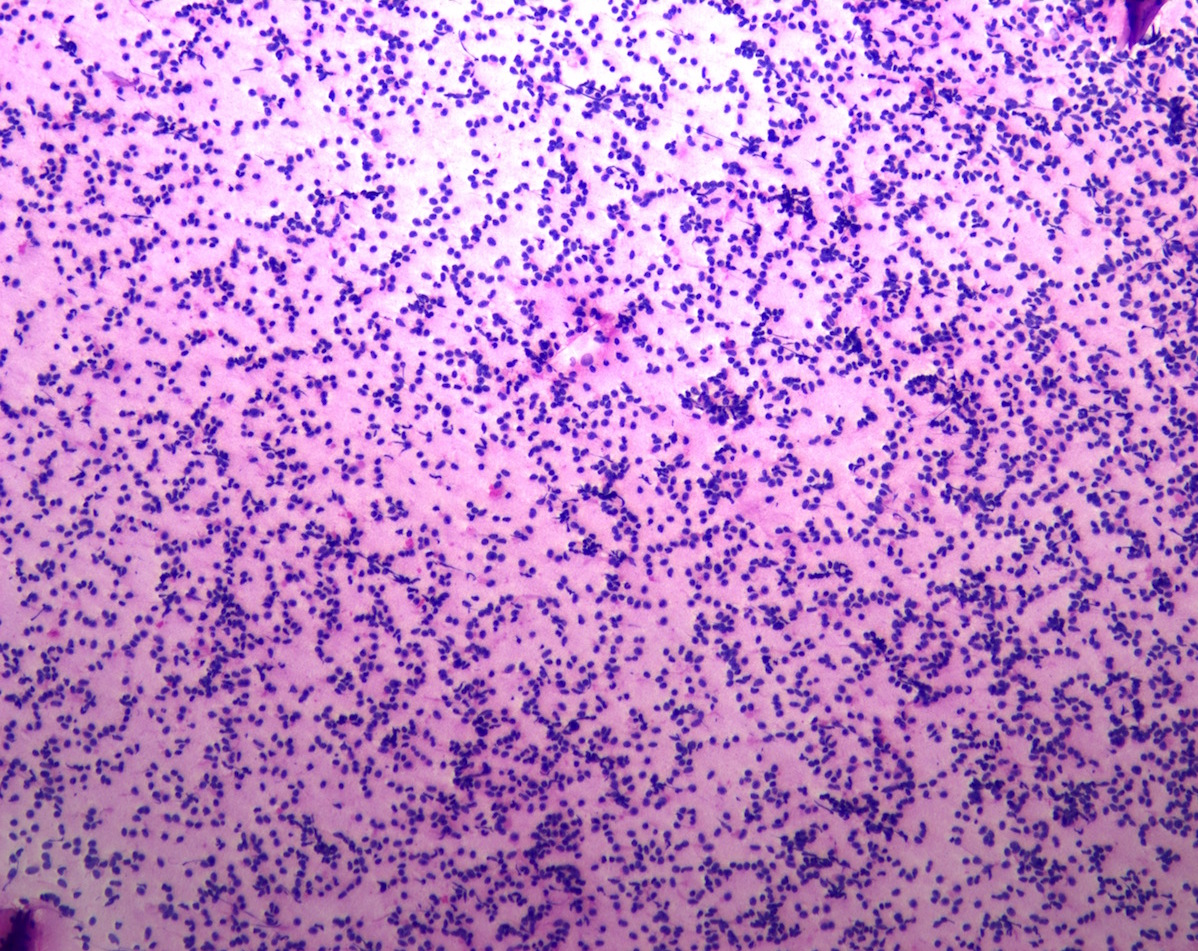

Cytology description

- Normal pituitary has mixed cell types on smear preparation whereas tumors show uniform morphology and cell type

- Tumors produce cellular smear with discohesive small round blue cells

- Some tumors have specific cytologic atypia (e.g., fibrous bodies of sparsely granulated somatotroph tumors, Crooke hyaline of Crooke cell tumors)

Cytology images